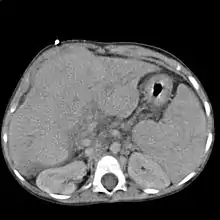

Scanner montrant une hépatomégalie sur un foie cirrhotique.

Le scanner et l'IRM sont meilleurs que l'échographie pour détecter un cancer du foie[2]. L'IRM est également fiable pour détecter certaines causes, notamment l'hémochromatose, par la mesure de la concentration en fer des tissus[15]. La fibroscopie œsogastrique peut retrouver des varices œsophagiennes, signe d'hypertension portale.